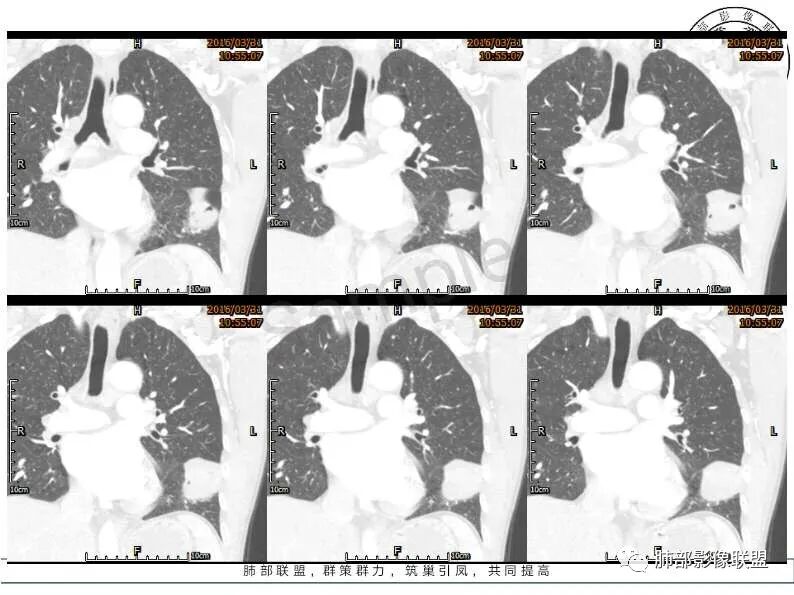

定位:肺内来源的病变,病灶下缘可见支气管进入病灶,部分支气管堵塞,冠状位可见宽基底向叶裂相贴,局部两端可见尾征,病变边缘平直,分叶,略彭隆,周围可见磨玻璃影,平扫密度均匀,增强后不均匀高强化,内部坏死不均匀,纵隔淋巴结肿大,66岁,男性,无症状,考虑:肺癌(鳞癌,腺癌,神经内分泌癌)

左肺见软组织密度肿块影,边界清晰,边缘浅分叶,期内密度不均,病灶跨叶间裂,增强扫描病灶内见坏死,考虑鳞癌可能。

病灶跨叶生长,病灶内见支气管影,边缘清楚,与胸膜脂肪间隙消失,增强不均匀高强化,内部不均匀,考虑胸膜来源恶性占位

发生于左肺胸膜下叶间裂的一个肿物,沿着胸膜下两端呈尖角状改变,平扫密度比较均匀,增强扫描可见片状坏死及不均匀的强化,可见支气管旁征,纵隔内有多发的肿大淋巴结,双色胸膜增厚,欠均匀。定位,来源于胸膜叶间裂的肿物,具有坏死,恶性的征象,考虑肉瘤,或恶性间皮瘤,纵隔淋巴结转移。鉴别诊断:孤立性纤维瘤,转移瘤.。

肿块呈梭型,叶间裂撑开,边缘清晰,提示来自斜裂胸膜,周围气体考虑是否假象,延迟强化,提示含纤维,考虑孤立性纤维瘤

病灶跨叶生长,与胸膜脂肪间隙消失,增强不均匀高强化,内部不均匀,旁边见空气半月征,纵隔见肿大淋巴结,考虑胸膜恶性肿瘤,肉瘤?

影像表现,左肺下叶病灶,密度不均匀,病灶与叶间胸膜关系密切,冠状位可见宽基底向叶裂相贴,局部两端可见尾征,病灶可见平直征,部分分叶表现,局部略彭隆,周围可见磨玻璃影,增强后不均匀高强化,纵隔多处淋巴结肿大,考虑:恶性病变或交界性病变,肉瘤或肉瘤样癌,孤立性纤维瘤(分化较差)。

平扫,3.9号,主体位于下叶,有胸膜凹陷,牵拉,有胸水。增强,3.31号,病灶整体缩小,并有突破叶间裂倾向,胸水消失,有占位效应,左下肺前基底段支气管推移,内部有液化坏死,有血管穿行(考虑肺内)。考虑肺内炎性病变,以炎肌母可能性大,纵隔淋巴结增大随诊。SFT,半个月不会变小

定位:肺内来源的病变,病灶下缘可见支气管进入病灶,部分支气管堵塞,局部成针孔征,冠状位可见宽基底向叶裂相贴,分叶,略彭隆增强后不均匀高强化,内部坏死不均匀,纵隔淋巴结肿大,66岁,男性,无症状,考虑:小细胞或神经内分泌癌

跨叶,包膜,定位肺外,叶裂;占位,膨隆,坏死,淋巴结肿大,定性恶性;起源:1、淋巴组织,淋巴瘤样坏死性肉芽肿?淋巴瘤?2,恶性SFT

男,66岁,体检发現。左肺跨叶裂肿物,下缘可见支气管进入病灶,部分堵塞,冠状位宽基与叶裂相贴,局部两端可见尾征,叶裂两侧生长不均衡,考虑肺内?肿物分叶,膨隆,周围可见磨玻璃影,平扫密度较均匀,增强后高强化,内部可见低密度灶,纵隔淋巴结肿大。考虑恶性,大细胞Ca?肉瘤?肉瘤样Ca?鉴别SFT、胸膜间皮瘤等。

左侧叶间裂梭形肿块,边缘膨隆,叶间裂无移位,增强渐进性强化,内可见蛇纹状血管,密度不均,内部坏死区边界欠清,纵隔多发肿大淋巴结,部分伴钙化,考虑1来源于叶间胸膜的肿瘤SFT。2间叶来源肉瘤。

肺窗太小,双侧肺透亮度相当,没有支气管堵塞,左下前段支气管姑且认为它通畅,肿块在前段的边缘。与肺内和胸膜的定位要仔细看前段,矢状位少许透亮,说明有一点代偿。远端可能有不张的肺组织,但支气管通畅,外压性。肿块边缘与胸膜成直角,提示胸膜压向肺内病变 ,纵膈肺门有淋巴结,sft是交界性肿瘤,可以。主体在胸膜,可以这样理解。这个病灶有沿斜裂生长趋势。

诊断:sft,交界性。

鉴别:肺内肿物,看下叶支气管是否完整。

处理:外科手术。